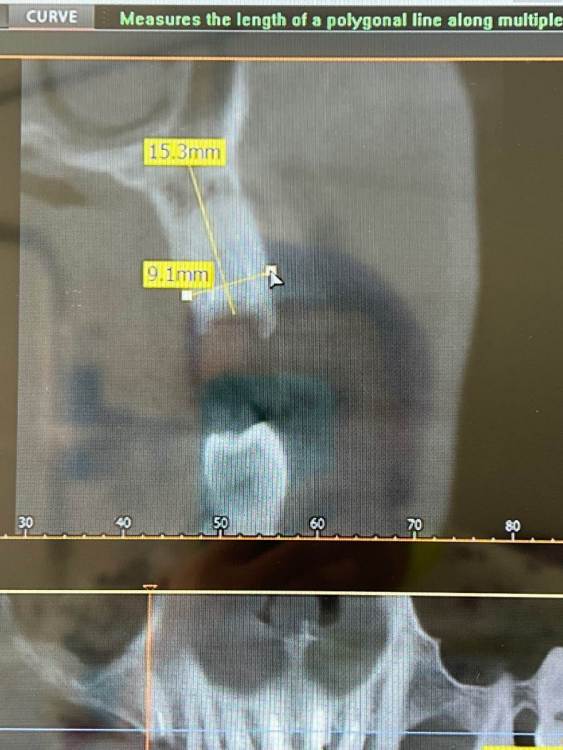

privetik Опубликовано 13 марта, 2024 Поделиться Опубликовано 13 марта, 2024 Добрый день коллеги . Имплантацией занимаюсь 4 года. Такой случай впервые . Мужчина 42 года без вредных привычек. Установлены 2 имплантата osstem 14зуб- 4,5 на 11,5 с одномоментным удалением корня; 15 зуб -4,5на 8,5; Торк на двух имплантах более 50 ньютон. Поэтому и поставлены сразу формирователи Через 10 дней после установки был на снятие швов, все было в пределах нормы! Позвонил на 14 день сказал, чувствует подвижность импланта в области 15 зуба. На осмотре слизистая в норме, имплантат подвижен. Пришел через месяц после операции с имплантом в руке. Слизистая отечная, гиперемирована. Гноетечения нет. Открыла лоскут, вся кость в фиброзе и около импланта 14. Он тоже подвижен!! Решила отставить и наблюдать. Все почистила, промыла. Положила кость мембрану. Все ушила. Вопрос в чем проблема? Почему так произошло. Сталкивались с таким впервые. Помогите пожалуйста советом. Ссылка на комментарий

red_butler Опубликовано 13 марта, 2024 Поделиться Опубликовано 13 марта, 2024 Здравствуйте, на фото сразу после инсталляции импланта, ФДМ уперся в края лунки, моя гипотеза, что это стало причиной лизиса кости и фейла. 4 Ссылка на комментарий